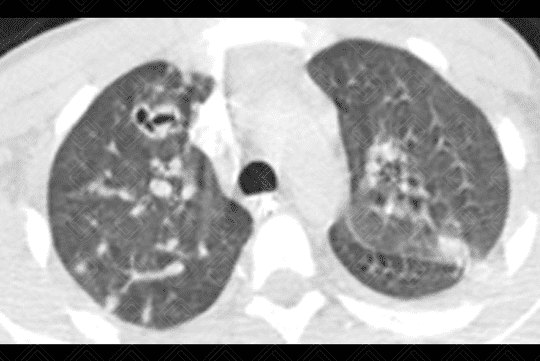

Descrição da lesão: Tomografia computadorizada do tórax (imagem axial e reformatação coronal) demonstrando opacidades nodulares bilaterais, esparsas e predominantemente periféricas, em vários estágios de escavação (setas vermelhas).

Embolia séptica: A embolia séptica pulmonar ocorre quando os fragmentos de trombo contêm microorganismos, em geral bactérias. Os principais fatores de risco incluem: uso de drogas intravenosas, presença de cateter intravascular, infecção generalizada, principalmente nos imunodeficientes, doença cardíaca congênita, tromboflebite séptica e processos supurativos da cabeça e pescoço. O agente mais comumente isolado em hemoculturas é o Staphylococcus aureus . Diante da suspeita clínica, podem ser solicitados radiografia ou tomografia computadorizada do tórax.

• Tomografia computadorizada do tórax: Nódulos em diferentes estágios de escavação, sendo mais numerosos na periferia dos pulmões e nos lobos inferiores. Podem ser observadas ainda consolidações geralmente subpleurais e cuneiformes.